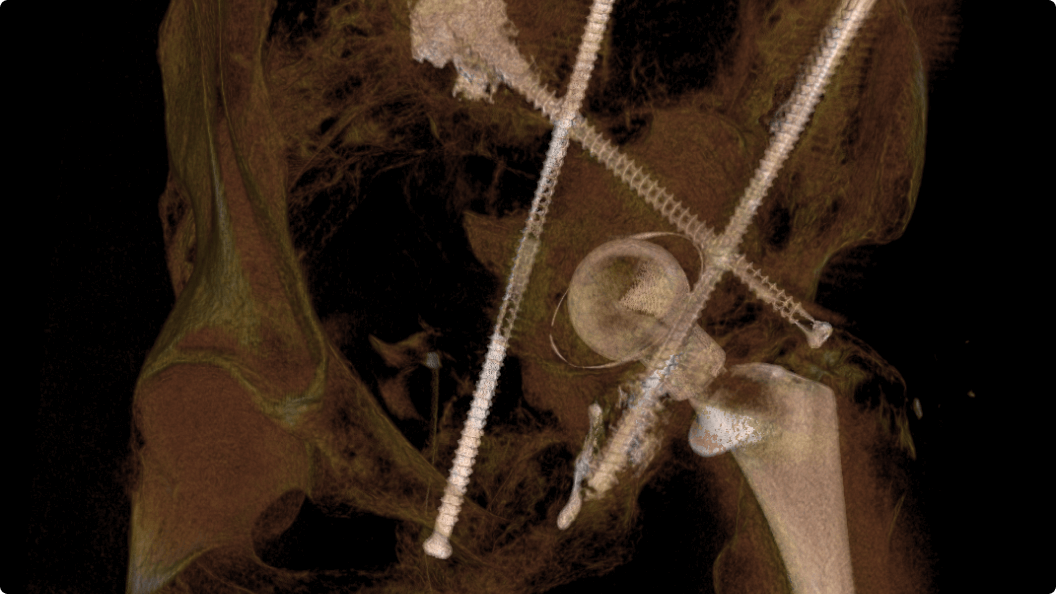

3D CT HD5

Optimierung von Diagnosen, chirurgischen Planungen, interventionellen Verfahren und Nachfolgeuntersuchungen

3D CT HD5 ist eine Option, die auf fortschrittlichen Algorithmen basiert. Diese Algorithmen verbessern die Visualisierung von Weichgewebe, reduzieren Rauschen und minimieren Artefakte, die den Visualisierungskomfort beeinträchtigen können. 3D CT HD bietet eine qualitativ hochwertige Bildgebung von internen Körperstrukturen einschließlich Gefäßen, Knochen und Weichgewebe. Mit dieser Funktion können Ärzte auf Aufnahmen von hoher Qualität zugreifen und fundierte Entscheidungen treffen.

3D CT HD5: Enhanced soft-tissue visualization and noise reduction for high-quality CBCT imaging